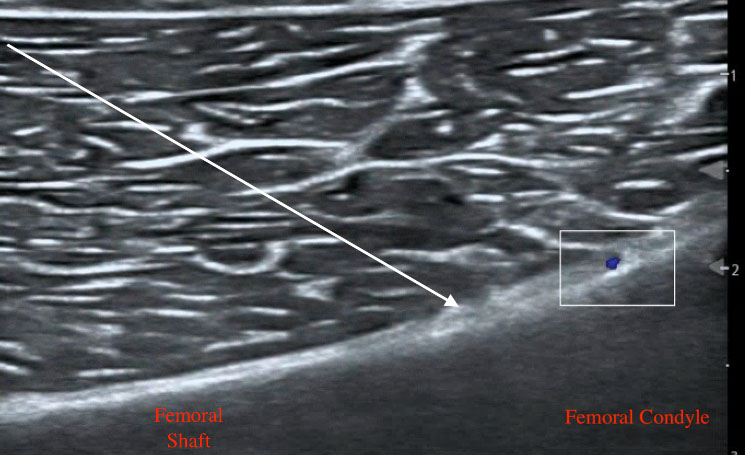

To target the SMGN, place the transducer on the medial aspect of the distal femur with the probe marker facing superiorly and identify the femoral shaft and femoral condyle. Another approach would be starting at the knee joint and moving superiorly to identify the femur bone. As the femoral shaft slopes superiorly, place color Doppler to identify the superior medial genicular artery. Advance a 20 gauge needle (or smaller) toward the slope avoiding the artery and make contact with bone. Inject 3-5 mL of local anesthetic lifting soft tissue and spreading along the periosteum.

Figure 3: SMGN ultrasound anatomy with needle trajectory indicated by arrow